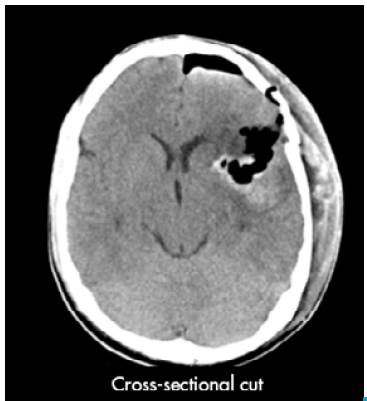

The patient was assessed by neurology, which requested a simple computed axial tomography (CT) of the brain, whose report suggested spontaneous intracerebral hemorrhage, described as a temporary lesion that displaces the midline and is accompanied by bleeding and perilesional edema (Figure 1). Various differential diagnoses were proposed, including brain tumor, glioblastoma, astrocytoma and middle cerebral artery aneurysm.

Simple computerized axial tomography of the brain prior to surgery.

Figure 1: Simple computerized axial tomography of the brain prior to surgery.

Source: Document obtained during the study.